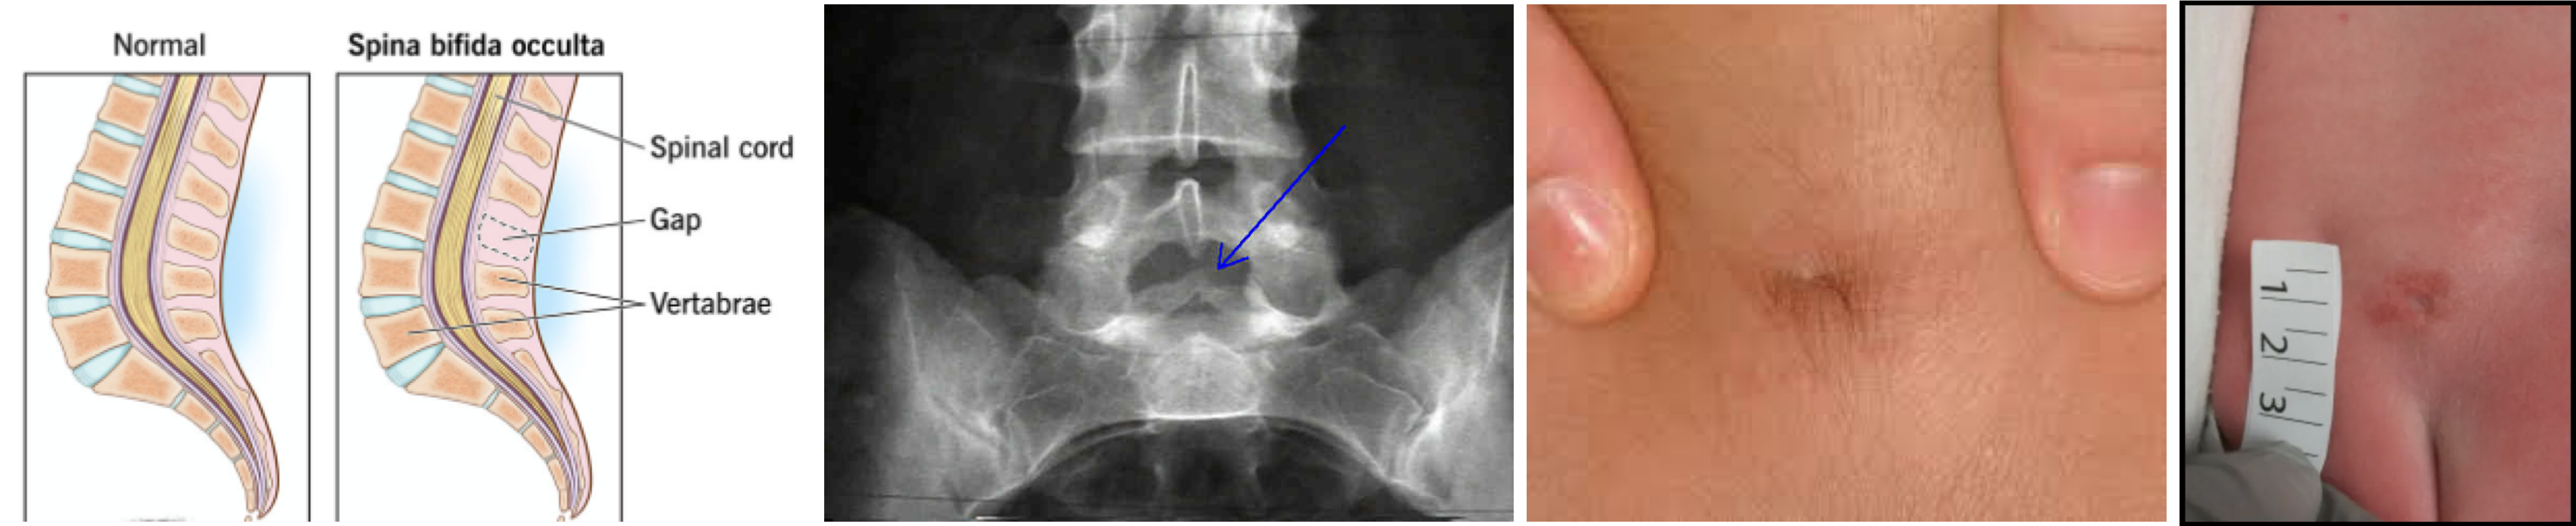

잠재 척추 이분증 (Spina bifida occulta)

가장 흔하고 경미한 형태. 척추뼈 아치의 결손만 있고 척수나 수막의 외부 돌출은 없음. 대부분 무증상이지만, 허리 부위에 dimple, 털, 지방종 등이 관찰될 수 있음.

선천성: Spina bifida occulta, lipomyelomeningocele, dermal sinus tract 등